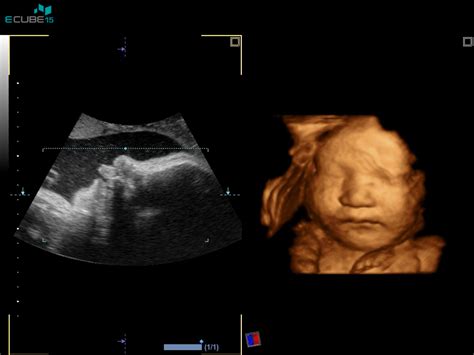

- Ultrazvočni pregledi: V času nosečnosti se opravijo trije ultrazvočni pregledi. Prvi je opravljen med 8. in 12. tednom nosečnosti, drugi okrog 20. tedna nosečnosti (morfologija ploda, ocena plodove rasti), tretji pa med 35. in 37. tednom nosečnosti. Če nosečnica na prvi pregled pride po 24. tednu nosečnosti, se opravita dva ultrazvočna pregleda.

Na željo nosečnice, vendar za plačilo, se lahko opravijo dodatne preiskave, kot so nuhalna svetlina z zgodnjo morfologijo ploda in dvojni hormonski test, četverni hormonski test, neinvazivni predrojstveni test (NIFTY), ultrazvočni pregled morfologije ploda, 3D/4D ultrazvočna preiskava, citološki bris materničnega vratu ob prvem pregledu v nosečnosti tudi izven strokovnih smernic, ter ultrazvočne slikice ploda in snemanje ultrazvočnega pregleda na zgoščenko.